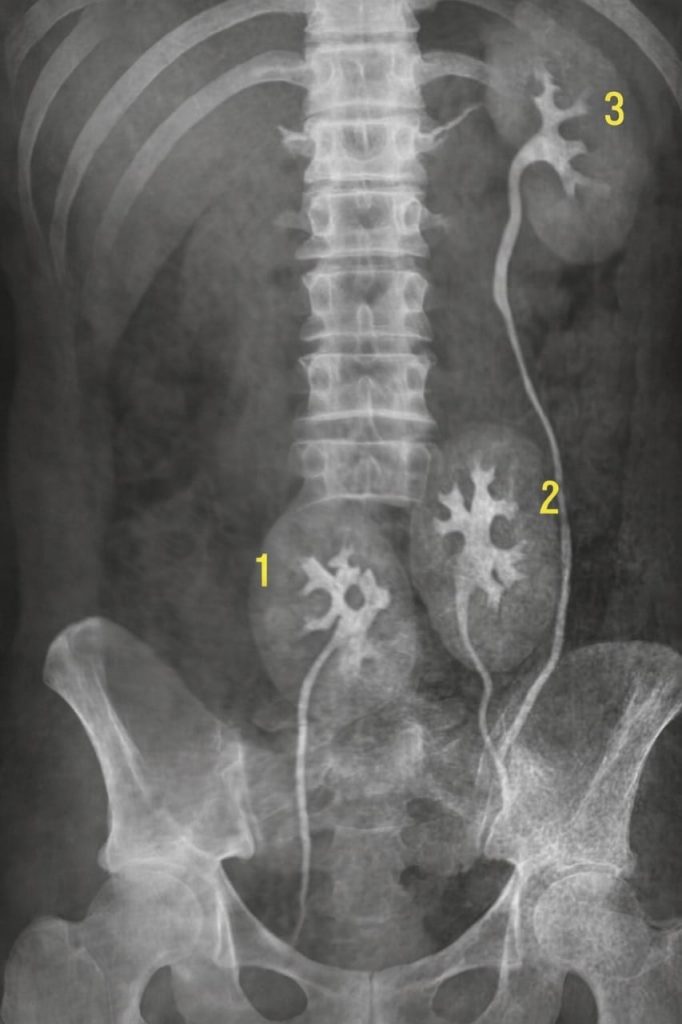

Na obrazovce byly dvě zřetelné siluety. Dva orgány vedle sebe, jako dva srostlé listy.

„Ne. Jsou to dvě ledvinové struktury. A obě jsou funkční.“

„Říká se tomu ‚přídavná ledvina‘. Je to velmi vzácný případ. Za celou dobu, co ji pozorujeme, bylo méně než sto takových popisů. Obvykle se nijak neprojevuje… jako ta vaše.“